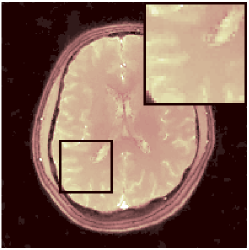

VI-E In-vivo experiments

Two sets of experiments were conducted here: first, we used the 2D and 3D acquisition sequences for scanning a healthy volunteer’s brain (real-world acquisitions). Figures 6 and 7 display the parametric maps reconstructed from 2D spiral and radial readouts. We computed the T1, T2 and proton density (PD) maps using baseline reconstruction algorithms ZF, VS, LR, FLOR, AIR-MRF and our proposed LRTV. While baselines use DM either for quantitative inference or also during reconstruction (i.e. AIR-MRF), we further compare the DM-free LRTV’s performance when cascaded to DM, KM and MRFResnet for quantitative inference. For the 3D spiral acquisitions we compared LRTV and its closest competitor VS in Figure 8. Outcomes from other tested algorithm are displayed in the supplementary materials (Figure S5). Since FLOR does not use dimensionality-reduction, our system ran out of memory during 3D reconstruction; hence results are not reported in this case.

VI-E1 Discussion

The LRTV-DM and LRTV-MRFResnet perform on par, and both outperform all tested baselines for reconstructing T1, T2 and PD maps in all acquisition schemes. This can be observed both visually in Figures 6, 7, 8, S2 and S3, and quantitatively in Table IV across all tested metrics. Other baselines were unable to successfully remove the under-sampling artefacts in TSMIs, and these errors propagated to the parameter inference phase and resulted in inaccurate maps. Temporal-only priors incorporated within LR are shown insufficient to regularise the inverse problem and LR sometimes (e.g. 2D spiral acquisitions) can admit solutions with even stronger artefacts than the model-free ZF baseline. This issue was previously studied for other non-Cartesian MRF readouts that similar to our spiral/radial trajectories, miss to sample the corners of the k-space in all timeframes (see section 2.2.2 and figure 2 in [19]). In the absence of reference for the k-space corners information, the LR iterations despite minimising the objective can converge to solutions with high-frequency artefacts, as visible in the computed maps. This highlights the need for adding an appropriate spatial-domain regularisation. FLOR reduces the LR’s artefacts but this improvement is limited because the suggested nuclear norm penalty does not incorporate an explicit spatial regularisation. Further for reducing artefacts, FLOR can introduce an undesirable bias in the computed T1/T2 maps e.g. see error maps in Figures S2 and S3. The non model-based VS baseline incorporates spatial regularisation and results in spatially smoother maps than ZF and LR, but it is unable to output artefact-free images. Further and consistent with our in-vitro experiment, we observe that VS overestimates the T2 values (e.g. in White and Grey matter regions) in tested 2D acquisitions i.e. the spatial regularisation trades off agains the quantification accuracy. The model-based AIR-MRF adds spatial regularisation through 2D/3D low-pass Gaussian filters however this trades off the sharpness of the computed maps and can increase the errors at the tissue boundaries (we searched Gaussian spreads that keep the blurs and high-frequency artefacts minimal). For our acquisition readouts, Gaussian filters performed better than disk filters of [19] for avoiding strong Gibbs artefacts. On the other hand, the spatiotemporally regularised LRTV greatly improves the TSMI reconstructions i.e. 4 dB enhancement compared to the closest competitor baseline (Table IV). This enables computing accurate and aliased-free multi-parametric inference using DM or the DM-free learning-based alternative MRFResnet as visible in Figures 6, 7, 8, S2 and S3. MRResnet and DM score competitive quantitative inference results i.e. T1 and T2 MAPE less than 5% and 9%, respectively (Table IV). KM also outputs comparably accurate T1 maps, however this shallow learning model despite having a model size larger than MRFResnet, is unable to learn accurate T2/PD quantification and it results in poor estimated maps, consistent with our observations in section VI-C.